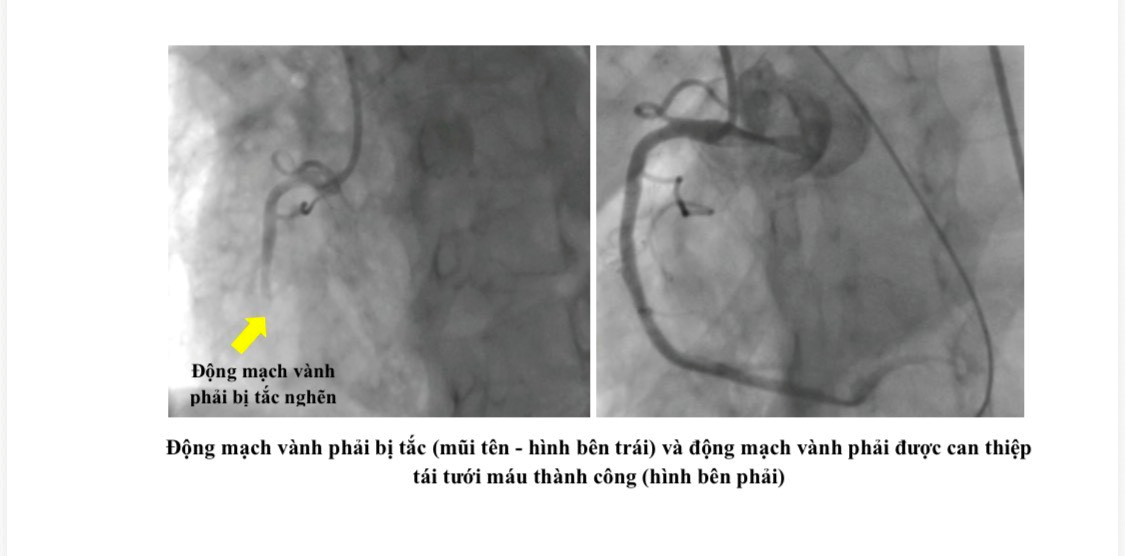

Tại đây, bệnh nhân được chụp mạch vành khẩn cấp và phát hiện có nhiều huyết khối gây tắc động mạch vành phải – là nguyên nhân chính gây ngưng tim trước nhập viện. Các bác sĩ Khoa Can thiệp tim mạch của Bệnh viện Nhân Dân Gia Định đã nhanh chóng đặt stent mạch vành và tiếp tục duy trì tuần hoàn ngoài cơ thể cho bệnh nhân. Hiện tại, bệnh nhân tỉnh táo, tiếp tục được theo hồi sức và dõi sát tại Khoa Hồi sức tim mạch.